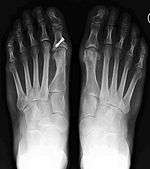

Syndesmosis procedure addresses specifically the two fundamental problems of metatarsus primus varus deformity that gives rise to the bunion deformity. They are leaning and instability of the first metatarsal bone . Syndesmosis procedure uprights the leaning first metatarsal bone with strong binding sutures between it and the second metatarsal bone (Fig. 2) and then also stabilizes it uniquely by creating a fibrous connecting bridge between these two bones (Fig. 3,4). First metatarsal bone can be readily realigned is because by definition of the metatarsus primus varus deformity its first metatarsal is abnormally loose and mobile.